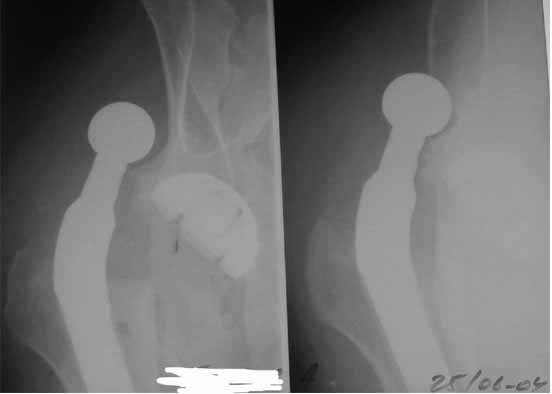

Сан Саныч,

Консультировать вывихи по рентгенограммам, не зная хода операции, дело не очень благодарное. Я думаю, что с датой операции Вы ошиблись и это был 2004 год? Тем не менее. Настораживают два фактора. Первое - не видно большого вертела. Если с мышцами обошлись грубо и их отсекли, то это очень грустно и нужна "связанная" пара, т.н. "constrain cup". Смущает хорошо прослеживаемый малый вертел и небольшая ретроверсия чашки. Возможно это (избыточная ретроверсия ножки и чашки) могло послужить причиной вывиха. Обычно гипсовая повязка после операции не накладывается, значит, были глубокие сомнения у оперировавшего хирурга. В этом случае - ревизия с перестановкой как минимум - ножки, а как максимум - обоих компонентов.

Но желательно бы знать ход операции.

Во вложении - рентгенограммы после вывиха и после вправления.